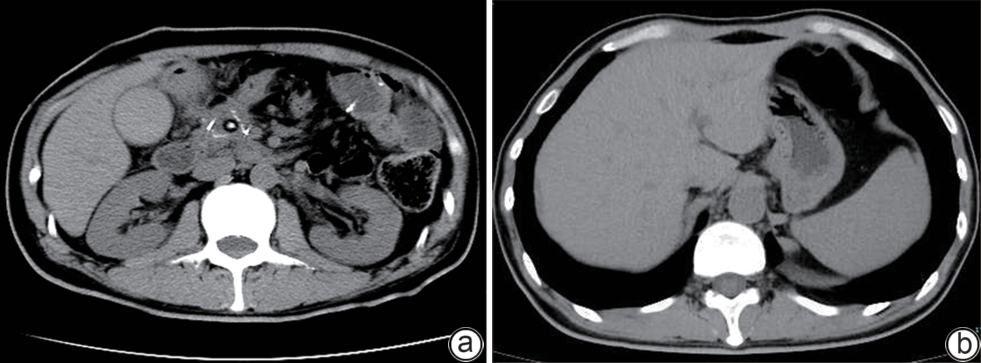

Impact of hepatocellular carcinoma on the prognosis of patients with liver cirrhosis undergoing emergency endoscopic therapy due to esophagogastric variceal bleeding

Xiaoqin ZHU, Na WEI, Yong XIAO, Baoping YU

2025, 41(2): 277-283. DOI: 10.12449/JCH250213

Abstract(2541) HTML (321) PDF (1277KB)(75)

Abstract:

Objective  To investigate the impact of hepatocellular carcinoma (HCC) on the prognosis of patients with liver cirrhosis undergoing emergency endoscopic therapy for esophagogastric variceal bleeding, as well as independent influencing factors for the prognosis of liver cirrhosis patients without HCC after emergency endoscopic therapy for esophagogastric variceal bleeding.  Methods  A total of 117 liver cirrhosis patients without HCC and 119 liver cirrhosis patients with HCC who underwent emergency endoscopic therapy for esophagogastric variceal bleeding in Renmin Hospital of Wuhan University from January 2017 to July 2023 were enrolled. Basic information including age and sex was collected from all patients, as well as the presence or absence of chronic diseases such as hypertension, diabetes, and coronary heart disease, the time of emergency endoscopy after admission, and liver function parameters including international normalized ratio, albumin, creatinine, sodium, total bilirubin, alanine aminotransferase, and aspartate aminotransferase (AST). The independent-samples t test was used for comparison of normally distributed continuous variables between two groups, and the Wilcoxon rank-sum test was used for comparison of non-normally distributed continuous variables between two groups; the chi-square test was used for comparison of categorical variables between groups. The covariance analysis and the multivariate logistic regression analysis were used for comparison of outcome variables after control of baseline variables, and the Kaplan-Meier survival curve was plotted for each group. The univariate and multivariate Cox regression analyses were performed for survival time in the non-HCC group to investigate the independent influencing factors for survival time, and then the Kaplan-Meier curve analysis and the log-rank test were performed to validate such independent influencing factors and analyze the independent influencing factors for secondary outcomes.  Results  Compared with the non-HCC group, the HCC group had significantly higher red blood cell transfusion units (6.00[2.00~9.00] vs 4.00[1.75~7.00], Z=-2.050, P=0.040, F=4.869, adjusted P=0.028), a significantly shorter survival time (29.77±16.01 days vs 38.07±11.43 days, t=4.574, P<0.001, F=17.294, adjusted P<0.001), and a significantly higher 5-day rebleeding rate (22.69% vs 6.84%, χ2=11.736, P<0.001, adjusted P=0.021). The Kaplan-Meier curve analysis showed that the risk of 42-day mortality in the HCC group was 3.897 (95% confidence interval [CI]: 2.338 ‍— 6.495, P<0.001) times that in the non-HCC group. The multivariate Cox regression analysis of the non-HCC group showed that the total length of hospital stay (hazard ratio [HR]=0.793, 95%CI: 0.644 ‍— ‍0.976, P=0.029) was an independent protective factor for 42-day survival. The Kaplan-Meier curve analysis showed that a length of hospital stay of >9 days was beneficial for the prognosis of patients (HR=4.302, 95%CI: 1.439 — 12.870, P=0.037). Blood sodium level (odds ratio [OR]=0.523, 95%CI: 0.289 ‍— ‍0.945, P=0.032) and MELD-Na score (OR=0.495, 95%CI: 0.257 ‍— ‍0.954, P=0.036) were independent protective factors against 5-day rebleeding, while AST level was an independent risk factor for 5-day rebleeding (OR=1.023, 95%CI: 1.002 ‍— ‍1.043, P=0.028) and in-hospital death (OR=1.036, 95%CI: 1.001‍— ‍1.073, P=0.045).  Conclusion  Liver cirrhosis patients with variceal bleeding and HCC tend to have a worse prognosis, and for the non-HCC group, in-hospital mortality rate increases with the increase in AST level. The total length of hospital stay is an independent protective factor for survival time in the non-HCC group, and it is recommended to appropriately prolong the length of hospital stay for such patients.